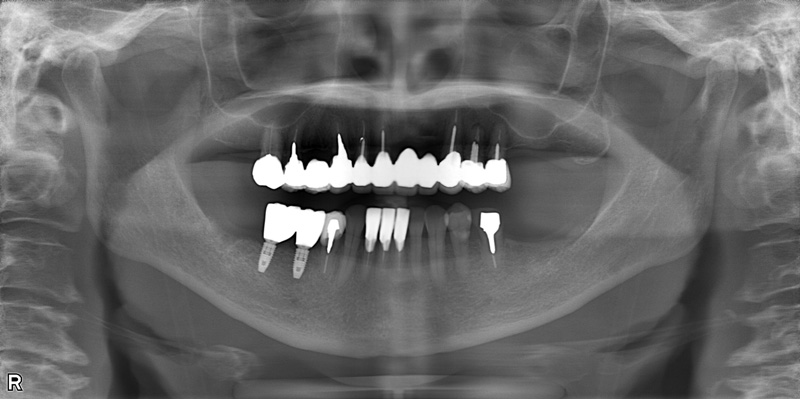

46歳女性

治療前

治療後

| 施術名 | インプラント治療 |

| 施術の説明 | インプラント治療とは、歯を抜いた所にチタン製の人工歯根を埋入し、新しく歯を入れる方法です。 |

| 施術の副作用 (リスク) | 腫れや疼痛を感じる、違和感を感じるなどの症状を生じることがあります。 |

| 施術の価格 | 53万円~+消費税 |